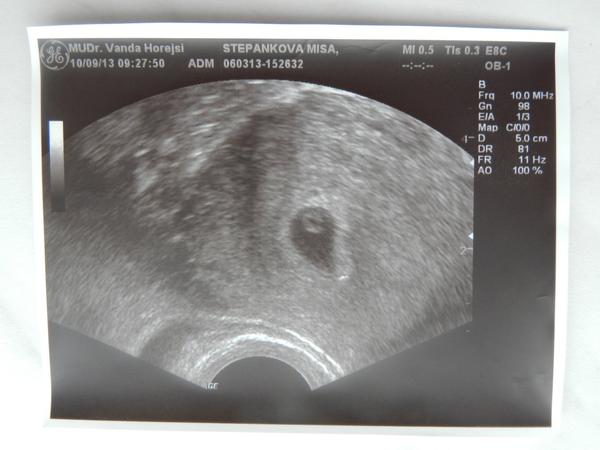

@juliemichal děkuju moc. já pořád porovnávám fotku syna s touhle fotkou a to jedno větší kdyby bylo přiblížené, tak by to bylo možná asi to samé, ale jak píšu, má nějaký straý přístroj a je to teda bída ty fotky :D . přikládám právě fotku syna v 5 týdnu z nabuseného přístroje.. . 😀